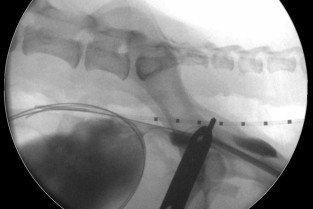

Le Groupe d'Étude en Chirurgie est heureux d’organiser sa 9è journée spécialisée sur le thème de la radiologie interventionnelle, le 29 janvier 2026. Cette journée annuelle de formation vise un public de vétérinaires ayant un fort intérêt pour la chirurgie des tissus et la chirurgie mini-invasive. Elle se tiendra au siège de l'AFVAC Paris 8è.

L’objectif de cette journée est d’élargir son champ de connaissances relatives à la chirurgie interventionnelle des carnivores domestiques, permettant de présenter les principales indications, le matériel indispensable et le déroulement des principales procédures. Le format de cette journée vise à favoriser les échanges avec les conférenciers et entre les participants, permettant à chacun de partager son expérience et ses difficultés.

- Connaître les principales indications de radiologie interventionnelle.

- Identifier le matériel nécessaire à chaque procédure.

- Connaître le principe du déroulement de chacune des procédures.